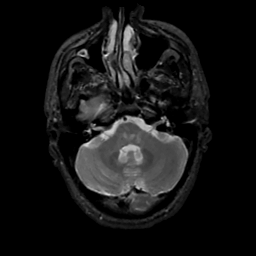

MR Study #1, February 10, 1991 -- Slice #11

[Home][Help][Clinical][Tour 1][Tour 2] Slice 11